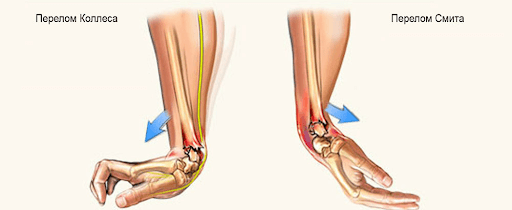

Перелом Коллеса

Один из наиболее распространенных переломов дистального отдела лучевой кости – «перелом Коллеса», при котором отломок (сломанный фрагмент) дистального отдела лучевой кости смещен к тыльной поверхности предплечья. Этот перелом был впервые описан в 1814 году ирландским хирургом и анатомом, Авраамом Коллесом.

Перелом Смита

Роберт Смит описал подобный перелом лучевой кости в 1847 году. Воздействие на тыльную поверхность кисти считается причиной такого перелома. Перелом Смита – это противоположность перелома Коллеса, следовательно, дистальный отломок смещается к ладонной поверхности.